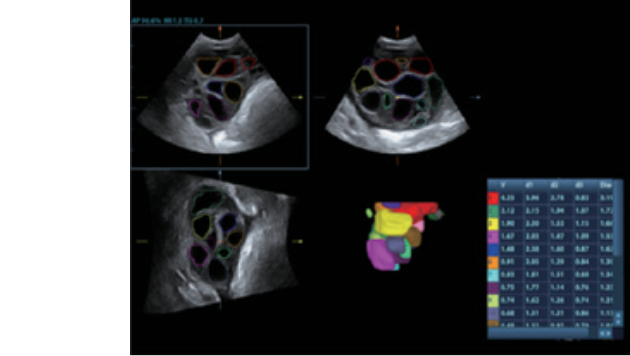

Cardiac_2D

Four chamber View

TT QA (vector)